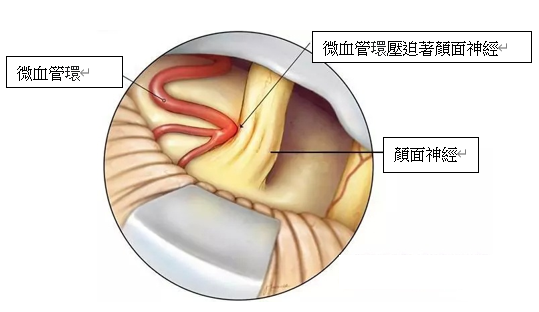

半边面肌痉挛症的病人多于中年后发病, 女性患病率比男性高。病因是由位于脑干的面部神经根出区域神经元受到外来压迫或刺激,导致神经线产生异常兴奋的错误神经讯号,尤如电线的短路现象一样,导致病人半边的眼眉或者面部肌肉不自主地抽搐。

全身麻醉下, 脑神经外科医生会在显微镜下, 在病人耳后的颅底骨进行手术, 手术并不是在大脑内部进行操作,而是利用人体组织的间隙、在脑组织与颅骨之间的蛛网膜下腔内进行手术, 因此不需要破开任何脑神经。脑神经外科医生会将压迫着颜面神经根部的血管隔开,并以人造海棉(Teflon) 将血管与神经永久阻隔,去除神经线短路的因由。手术的治愈率达到80-90%上,复发率约10%,严重的并发症 (如听觉神经功能失聪) 的风险的发生率侧为2%。